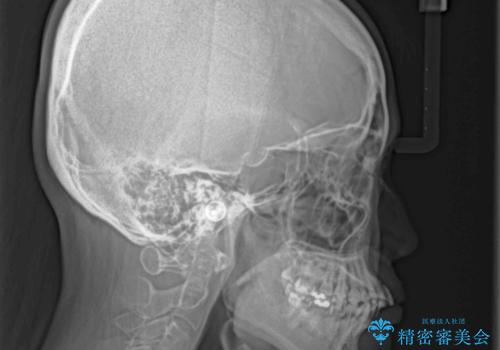

- 上下の歯の前後関係が乱れ、歯に負担がかかるとのことで来院された患者様です。

下顎が右左側に変位しているため、左側奥歯の咬み合わせが上下反対の関係となっていました。

また、上下ともに歯列が狭窄しており、奥歯以外にも反対咬合が認められました。

歯列全体の拡大と、歯と歯の間を削ることでスペースを獲得し、インビザラインによる矯正治療を行うこととしました。